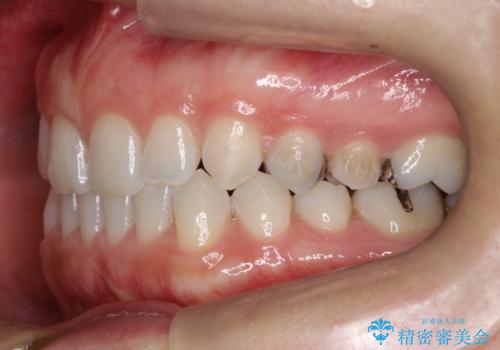

- 前歯の正中離開(すきっ歯)の改善を希望され来院された患者様です。

初診時の歯並びの状態としては、上顎中切歯間に1mm程の隙間があり、その他に見た目に関して気になるような問題点はない状態でした。

インビザライン(マウスピース)にて上顎のみの矯正治療を行いました。